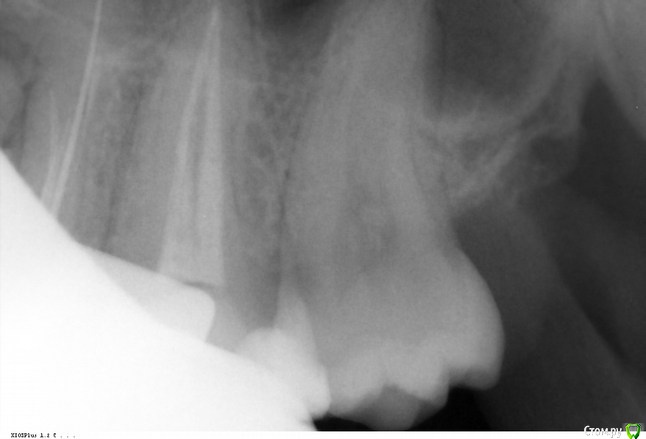

Викторри Опубликовано 17 февраля, 2018 Автор Поделиться Опубликовано 17 февраля, 2018 (изменено) Уважаемые доктора! Помогите прояснить ситуацию: может ли зуб с кистой(26) реагировать на горячее-теплое либо стоит искать проблему в другом зубе? боль в области 26-28. могу прикрепить кт. Спасибо.Также есть снимок 26-28 от 11.12.2017 Изменено 17 февраля, 2018 пользователем Викторри Ссылка на комментарий

Викторри Опубликовано 18 февраля, 2018 Автор Поделиться Опубликовано 18 февраля, 2018 Беспокоит чувствительность только на тепло?8 недель уже каласепт? Ничего не меняется?Спасибо за ответ.На горячее-теплое, у меня впечатление,что не меняется. Каласепт уже 8 нед. Причем боль возникает не сразу при приеме горячего, а запоздало, постепенно расходится, как будто из эпицентра .Отчетливее всего она в 27 зубе,потом проходит. Мой лечащий врач утверждает,что реагирует выдвинувшийся 26 зуб именно у десны, моя постоянная врач говорит,что это 26 ,кто-то -за 28. Извините, что много ?. Насколько я поняла,при раскрытии кисты боль должна была пройти, но не прошла. Может ли быть причиной 28 зуб (там неск-ко врачей видели полость по рг) или все-таки проблема 26? На завтра мне назначена пломбировка 26 зуба. Насколько я поняла для пломбировки канал должен быть сухой ,соответственно если он не сухой, там есть проблем? м.б.,что каласепт не помог в течение такого времени или кисты могут долго болеть? Прикрепляю кт от 08.11.2107.Помогите разобраться: пломбироваться и ждать исчезновения болей или сейчас искать другой источник проблемы и после пломбир? Ответственность в принятии решения на мне, важно услышать ваше мнение. Спасибо. Ссылка на комментарий